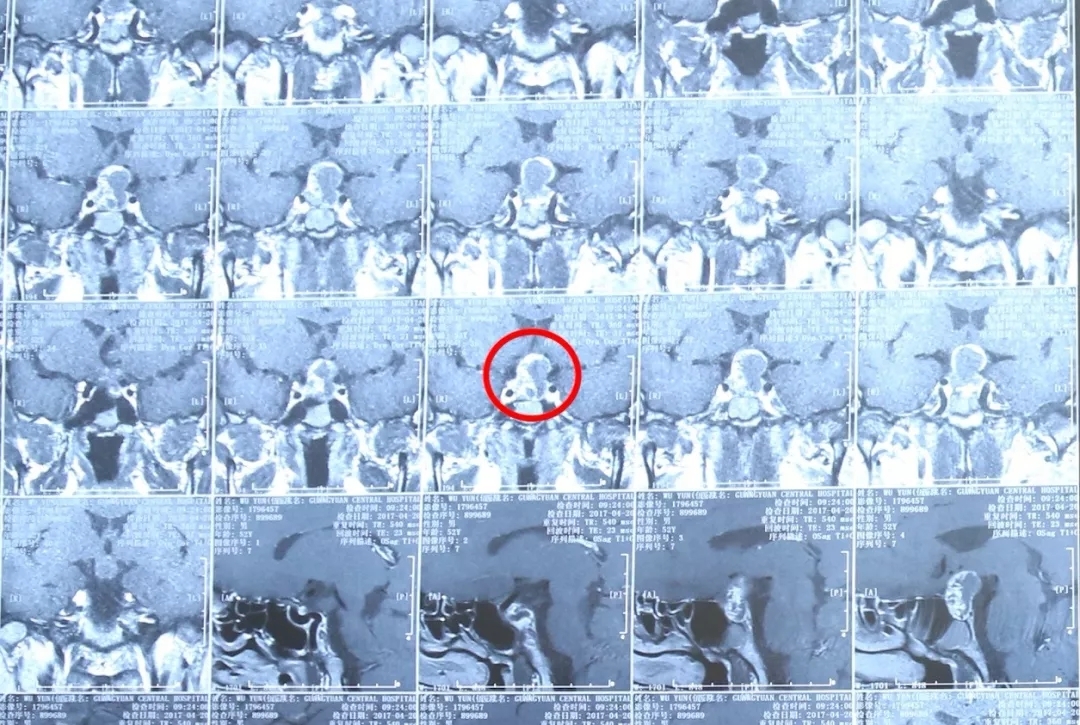

04 颅咽管瘤

颅咽管瘤为先天性肿瘤,约占颅内肿瘤的5%。多见于儿童及少年,男性多于女性。临床常表现为颅内压增高、双侧视力减退、视野缺损、精神不振、嗜睡、记忆力减退、反应迟钝、思维混乱、多饮多尿等。

颅咽管瘤患者MRI